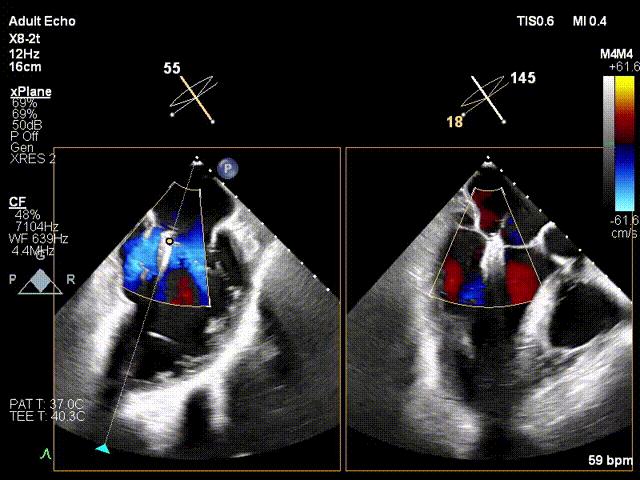

1. 术中基线评估三尖瓣反流程度

术中基线

5. 夹合后反流评估

反流